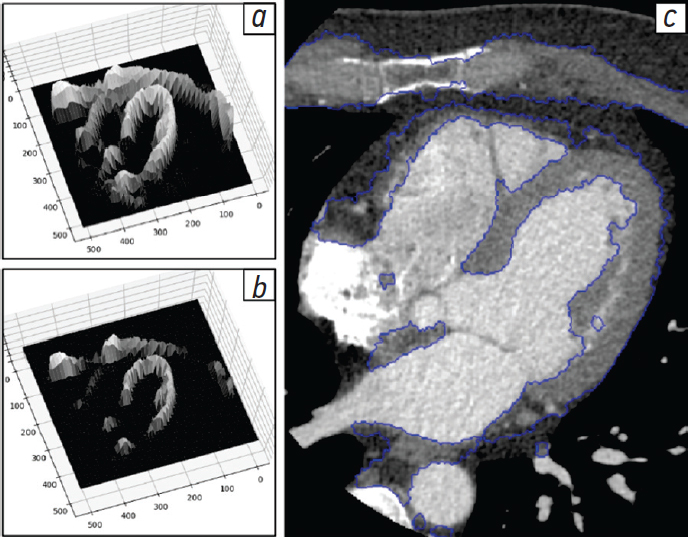

Для сегментации структур, имеющих относительно неравномерное распределение рентгеновской плотности (как, например, участок миокарда на представленной томограмме), может быть применен метод морфологических водоразделов [17]. Он заключается в определении локальных минимумов яркости на изображении с последующим построением границ между ними в местах, где начинает соединяться между собой вода, условно заполняющая яркостный рельеф из этих минимумов (рис. 4, а, b). Преимуществом данного метода в сравнении с методом обнаружения контуров является получение замкнутых областей. К недостаткам можно отнести высокую вычислительную сложность, а также чувствительность к локальным максимумам, что, в свою очередь, может привести к избыточной сегментации (рис. 4, c).

Рис. 4. Сегментация методом морфологических водоразделов: а — яркостный рельеф исходного изображения (изображение нормализовано в диапазон 256 градаций серого, значения яркости более 127 заменены на 0); b — заполнение рельефа «водой» до значения яркости 80; c — результат сегментации